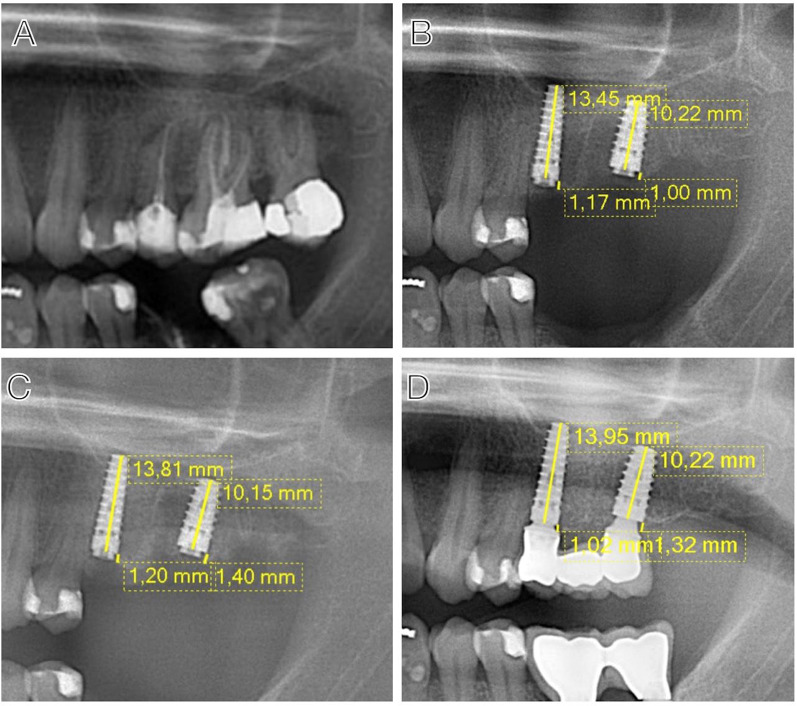

Purpose: The aim of this study was to evaluate the marginal bone loss (MBL) over a follow-up period of up to 36 months in Immediate dental implants (IDIs), as well as the impact of various clinical variables on the MBL.

Methods: IDIs placed in two surgical phases were evaluated. Implants were classified into bone loss (BL, exposed threads), bone remodeling (BR, crestal bone at the implant margin ± 0.1 mm), and bone overlapping (BO, bone above the abutment).

Results: A total of 1,040 IDIs were inserted in 344 patients with a successful osseointegration rate of 98.9%. The average MBL at 2, 6, 12, 24, and 36 months was - 0.3 ± - 1.0 mm, - 1.1 ± -1.8 mm, - 1.4 ± - 1.8 mm, - 1.7 ± - 1.9 mm, and - 1.3 ± - 2.3 mm, respectively. In the Baseline-12-month period, 17.5% of the IDIs presented BL, 9% BR, and 73.5% BO. For the B1-12 month period, 19.8% presented BL, 10.7% BR, and 69.5% BO. Mixed regression models showed significant MBL overtime pre-loading (p < 0.0001), stabilizing at 8.5 months from implantation. Immediate mandibular implants had lower MBL (p = 0.0365). Post-loading, MBL was lower in the mandible (p = 0.0095) and positively influenced by abutment height and rotational abutments.

Conclusions: The present study supports the clinical efficacy of the IDIs placement protocol with high survival rates and acceptable MBL. It is recommended to place bone level implants slightly below the crest to ensure the platform remains at an optimal depth during the initial bone remodeling phase post-implantation.